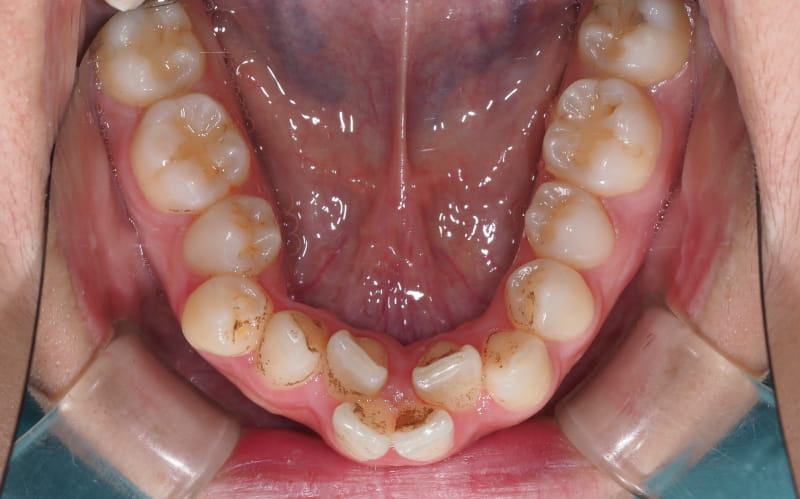

二、如果第一步判斷需要正畸治療,那麼就要檢查牙齒的情況,進行臨床資料的採集,隱形正畸需要的資料包括但不限於口掃、拍攝口腔全景的X光片、面像照以及口內照等視覺數字化檢查項目。

牙齒矯正案例 – 1

牙齒矯正案例 – 2

牙齒矯正案例 – 3

牙齒矯正案例 – 4

牙齒矯正案例 – 5

牙齒矯正案例 – 6

牙齒矯正案例 – 7

牙齒矯正案例 – 8